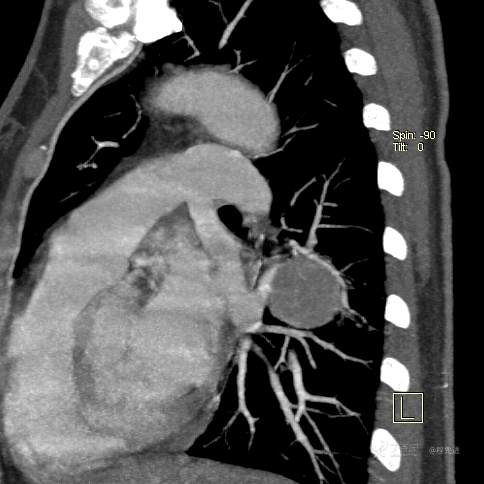

CT增强

平扫CT值约40HU(未上传图像),增强后动脉期CT值约70HU,静脉期CT值约97HU。